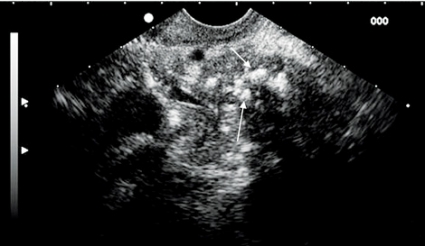

Vid misstänkt sten i gallgångarna har endoskopiskt ultraljud en sensitivitet och specificitet som är högre än 95 procent för detektion av koledokussten [17] (Figur 11). Endoskopiskt ultraljud har högre sensitivitet än transabdominalt ultraljud (25–63 procent) och likvärdig sensitivitet med ERCP men utan samtidigt ökad risk för pankreatit.

Vidare har kontrollerade studier av endoskopiskt ultraljud och MRCP visat att endoskopiskt ultraljud är lika bra eller bättre för att diagnostisera stasikterus och koledokussten [18]. En aktuell översiktsartikel har föreslagit att endoskopiskt ultraljud skulle kunna vara förstahandsmetod för att undersöka gallvägarna hos patienter med intermediär misstanke om koledokussten.